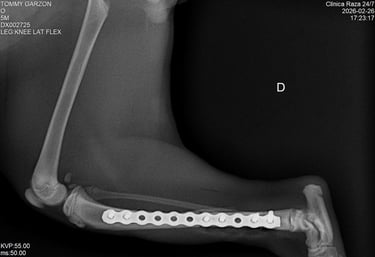

Un sistema de placa bloqueada es una técnica avanzada de fijación interna en la que los tornillos se bloquean directamente a la placa, formando una estructura rígida y estable.

A diferencia de las placas convencionales, este sistema no depende de la compresión contra el hueso, lo que permite:

Fijación de la placa al hueso

La placa se posiciona sobre el hueso afectado, adaptándose a su anatomía sin necesidad de comprimirlo directamente.

Inserción de tornillos bloqueados

Los tornillos se introducen atravesando la placa y se enroscan en ella, quedando firmemente anclados tanto al hueso como a la placa.

Formación de un sistema rígido

Al bloquearse los tornillos con la placa, se crea una estructura estable tipo “armazón” que no depende de la presión sobre el hueso.

Estabilización y cicatrización ósea

El sistema mantiene los fragmentos óseos alineados, permitiendo una adecuada recuperación y favoreciendo la cicatrización.